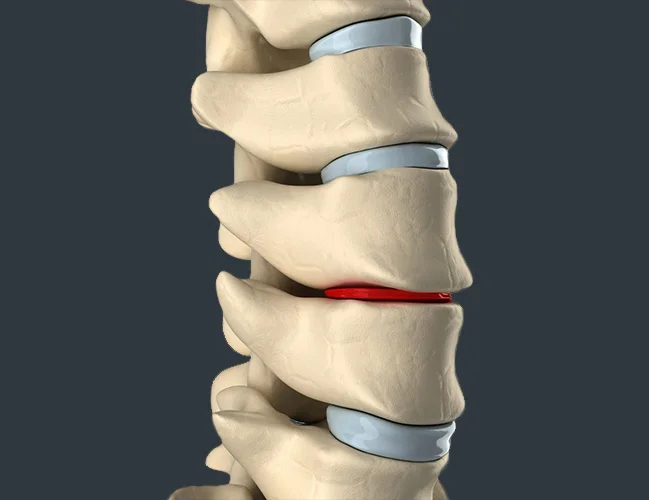

A herniated disc, also referred to as a slipped disc, ruptured disc, or disc herniation, is one of the most common causes of back pain. Often, people visit a spine specialist for back pain and unknowingly have a herniated disc. Herniated discs affect the vertebrae, the bones that make up your spine, and the spinal discs, which provide support and flexibility to your back.

Degenerative Disc Disease is a condition that causes pain, most commonly lower back pain, due to degeneration of the discs in the spine. Degenerative disc disease is actually one of most common causes of lower back pain and often goes undiagnosed for a long period of time.

Lumbar degenerative disc disease involves the breakdown of discs and facet joints in the lower back, often causing tenderness, leg weakness, and chronic pain.

Lumbar disc herniation happens when discs between vertebrae shift or rupture, compressing spinal nerves. Symptoms include lower back pain, leg weakness, and numbness.

Spondylosis is age-related degeneration of spinal joints, discs, and vertebrae, often causing stiffness, back pain, and abnormal spinal motion.